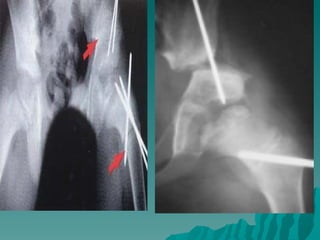

2- Femoral Osteotomi  Grafide sadece abduksiyon ile femur başı asetabulum ilişkisi (conainment) yeterli ve tatminkar oluyor ise femoral varus osteotomisi endikasyonu vardır

3- Innominate Osteotomi  Asetabular çatının yeniden yönlendirilmesi ile femur başının anterolaterali daha iyi örtülebilir.